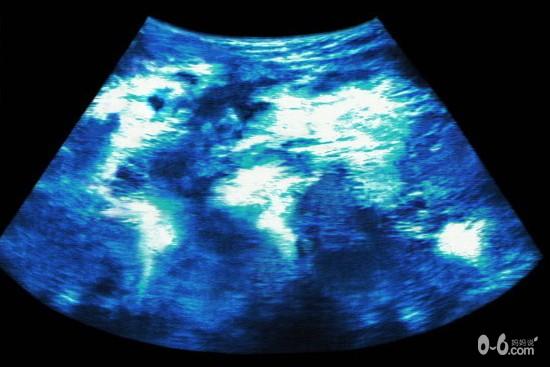

2D超音波显现出来的画面,必须是经过专业训练的医护人员,才有办法看出个所以然,也因此造成妈妈的疑虑。孙三源院长说,一般孕妇在接受产检超音波时,医师都会边照边说明,让孕妇也有参与感,也比较放心。但是,通常也只能告诉孕妇「这是手、脚。」或是「这是弟弟的小蛋蛋。」。却不能肯定的告诉孕妇,「手指都是5指,而且没有相连。」孙三源院长指出,透过超音波检查可以协助医师了解子宫内胎儿的状况,但是却无法得知,胎儿的智力、视力或听力等生理功能,是否正常的信息。

孙三源院长表示,产检时使用超音波检查,只是一种筛检方式,而非最终的诊断,一般有异常状况,可以被超音波筛检出来的机率也只有80%。其原因要归咎于超音波的特性,以及胎儿的成长状况。

1声波:超音波是一种耳朵听不见的声波,必须透过水当作介质,并且无法穿透骨头,而若是脂肪较厚亦会妨碍检查。

2.分辨率:超音波的分辨率,无法辨识出胎儿微小的缺陷。例如:较小的心室中隔缺损或动脉弓狭窄,不易由超音波诊断。又如神经管缺损通常位于尾脊皮肤的小破洞,产前也不容易发现。因此,若有羊水量过多或过少、胎儿周数较大骨头已钙化、妈妈肚皮脂肪较厚等状况时,胎儿的细部构造都无法看清楚。